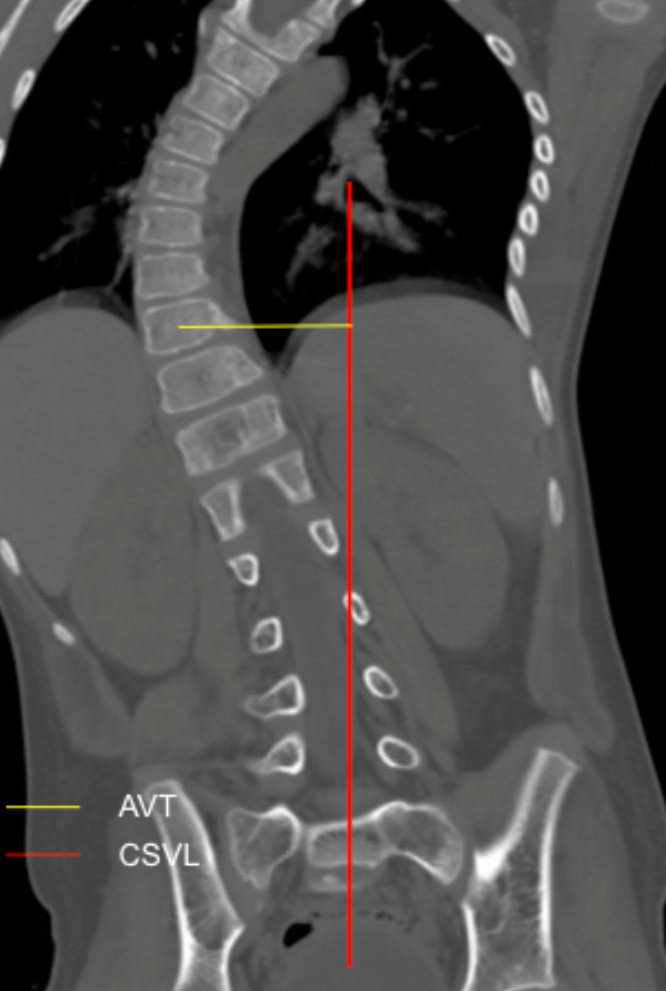

Apical Vertebral Translation (AVT) measures the horizontal distance between the midpoint of the apical vertebral body and the Central Sacral Vertical Line (CSVL). It reflects the magnitude of coronal plane deformity in scoliosis and is widely used to assess curve severity, progression, and surgical correction.

1. Draw the CSVL

• Identify the midpoint of the superior endplate of S1.

• Draw a vertical line upward from this midpoint perpendicular to the sacral base — this is the CSVL.

1. Identify the Apical Vertebra

• Locate the vertebra that is most laterally deviated from the CSVL in the lumbar curve.

1. Mark Vertebral Midpoint

• At the apical vertebra, mark the midpoint of the vertebral body.

1. Measure Translation

• Measure the horizontal distance (mm) from the apical vertebral midpoint to the CSVL.